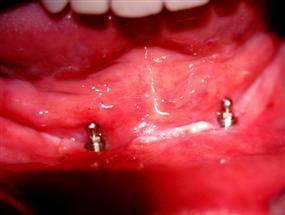

Muž, 67 let, nosil několik let snímací protézu, která se při jídle i mluvení stále uvolňovala, byla zcela nefunkční. Řešení: byla zhotovena tzv.hybridní protéza, která byla kotvena ke dvěma implantátům pomocí zásuvných spojů („patentků“). Jedná se o velmi funkční, rychlé a ekonomicky výhodné řešení.

Implantáty s kulovou hlavou v dolní čelisti

Hybridní protéza

Náhrada v ústech